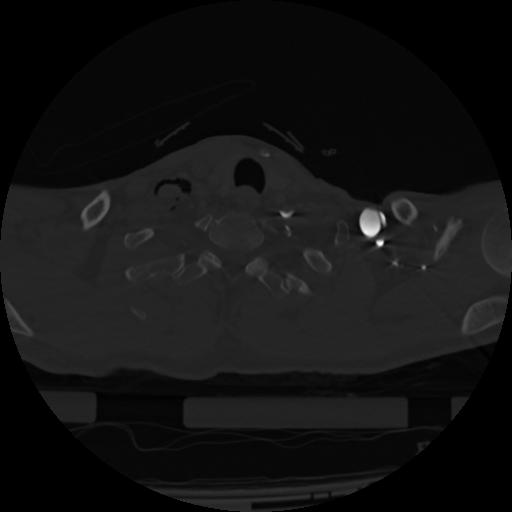

22 ANGIO,CE,Vol,0.5,ANGIO,,